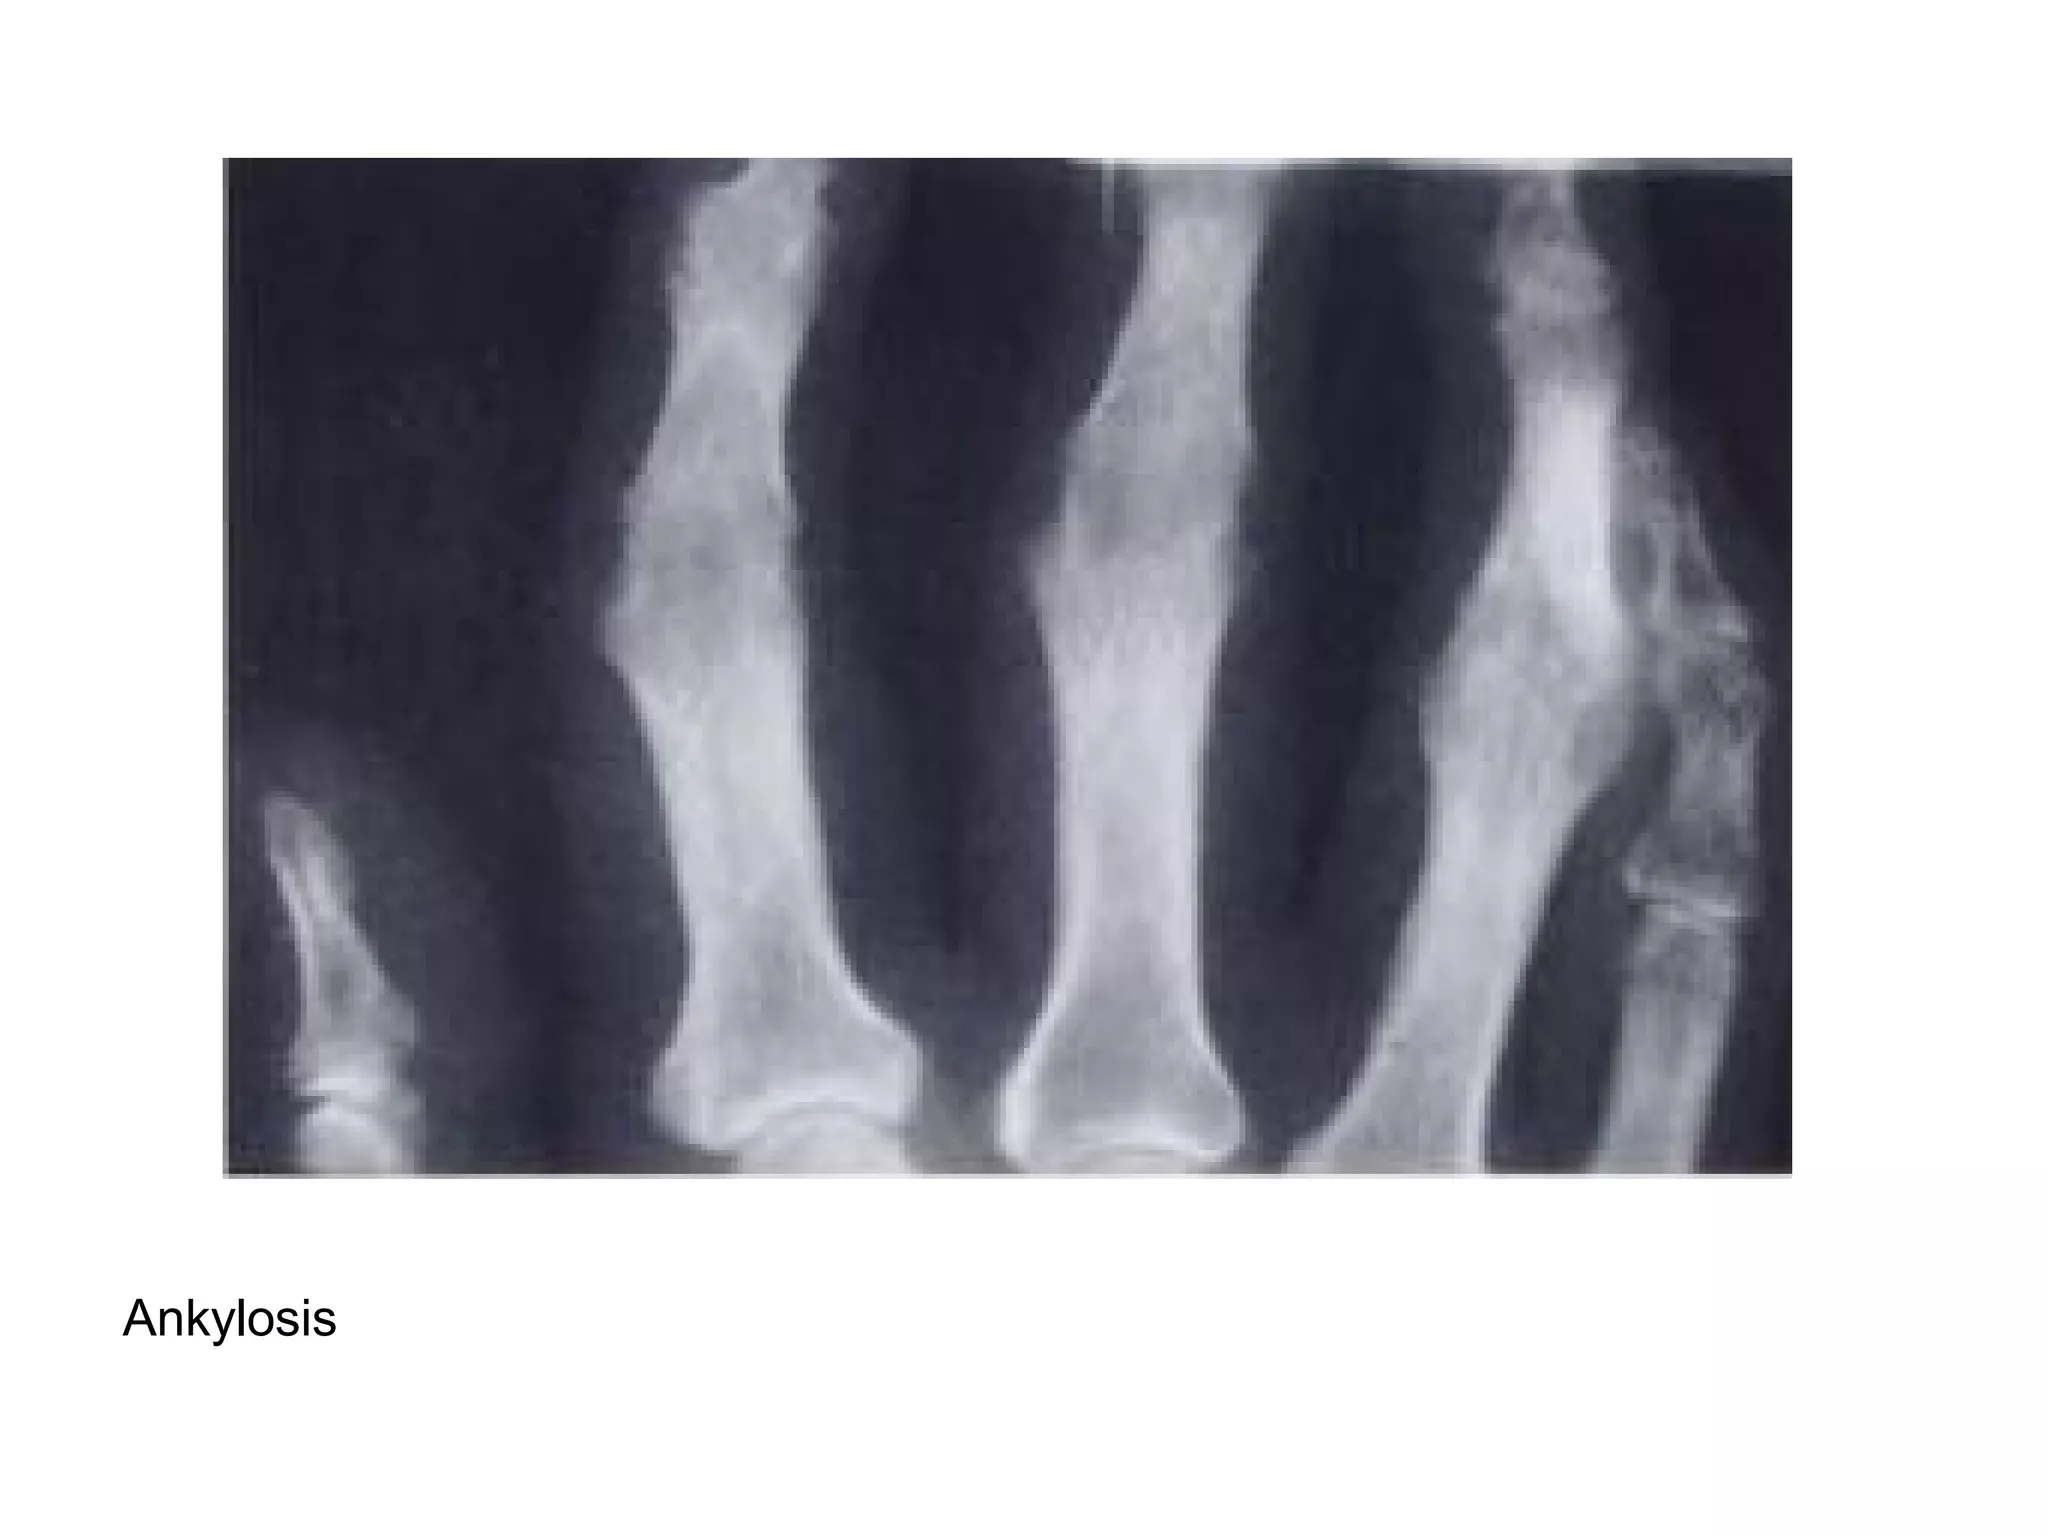

Joint ankylosis

Ankylosis